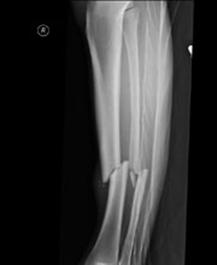

Fracturi simple: SPIRALA OBLICA TRANSVERSALA

Fractura spirala de Fractura transversa de diafiza femurala Fractura spirala de diafiza tibiala

diafiza humerala

Fractura spirala de diafiza tibiala Fractura oblica de diafiza tibiala Fractura transversala de diafiza tibiala

Fracturi cominutive

Fracturi spirala cominutive de Fractura complexa de diafiza radiala diafiza humerala